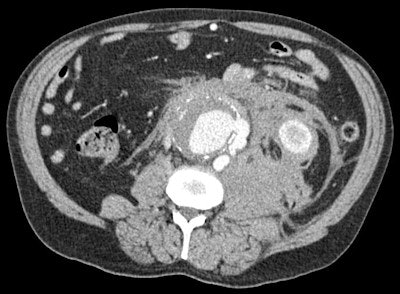

The radiological report, therefore, should provide clinically relevant information with quantitative and qualitative data, ideally presented in a graphic, analytical display. When monitoring response to treatment, concrete numbers should prove effect, such as chemotherapy reaction in specific patients. Advice should be useful and succinct. Furthermore, reports should be delivered in a timely fashion, or radiologists risk damaging their connection with their clinical partners.